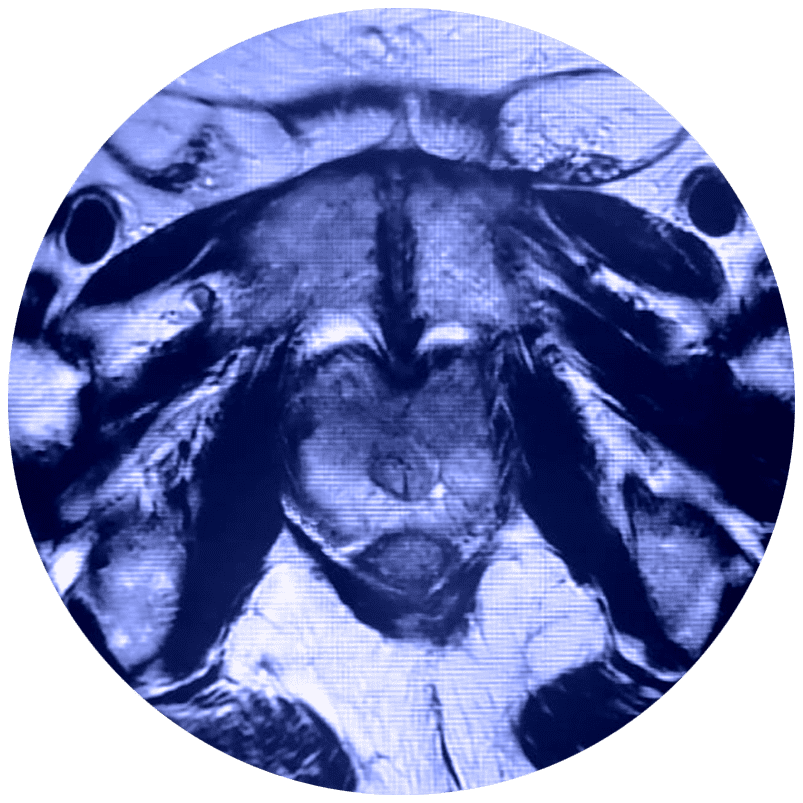

El estudio de Resonancia Multiparamétrica de Próstata no requiere de exposición a la radiación, evalúa el movimiento de las moléculas de agua (denominado difusión del agua) y el flujo sanguíneo (denominado imágenes de perfusión) adentro de la próstata. Esto ayuda al médico a diferenciar entre el tejido enfermo y el tejido sano de la próstata.

El médico utiliza la RMN para evaluar el cáncer de próstata y ver si se encuentra confinado a la próstata. La Mp-MRI proporciona información acerca de las moléculas de agua y del flujo sanguíneo a través de la próstata. Esto ayuda a determinar si el cáncer se encuentra presente y, si es el caso, si es agresivo y si se ha diseminado.